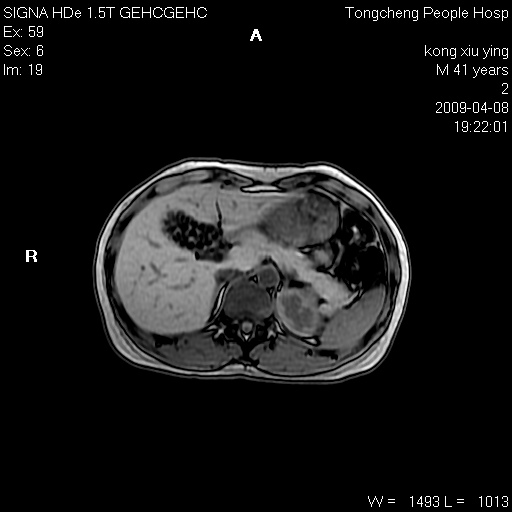

标题: CL1008:【经典】胆囊石榴籽样结石。 [打印本页]

标题: CL1008:【经典】胆囊石榴籽样结石。

女,41岁。健康体检——彩超提示:胆囊显示不清。平素健康,无不适感。

腹部mr扫描及mrcp,图像如下:

胆囊石榴籽样结石。